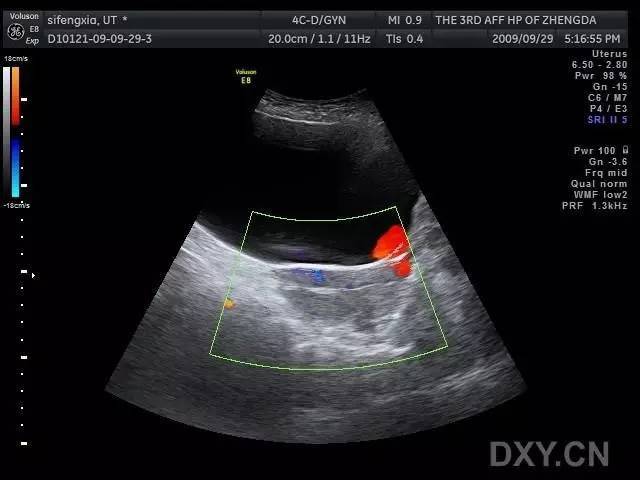

子宫穿孔的超声诊断

子宫穿孔彩超下表现

子宫穿孔超声表现图